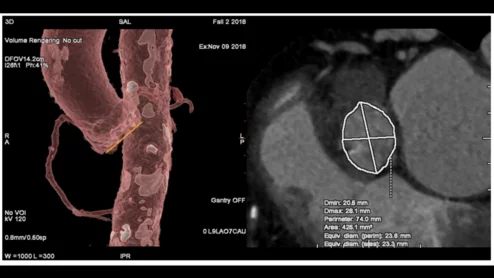

TAVR planning with GE Healthcare's Valve Assist 2 technology

Planning ahead of TAVR procedures with semi-automated sizing software helps cardiologists match each patient with the best device possible; not undersized or oversized, but something in the middle that would make Goldilocks proud.